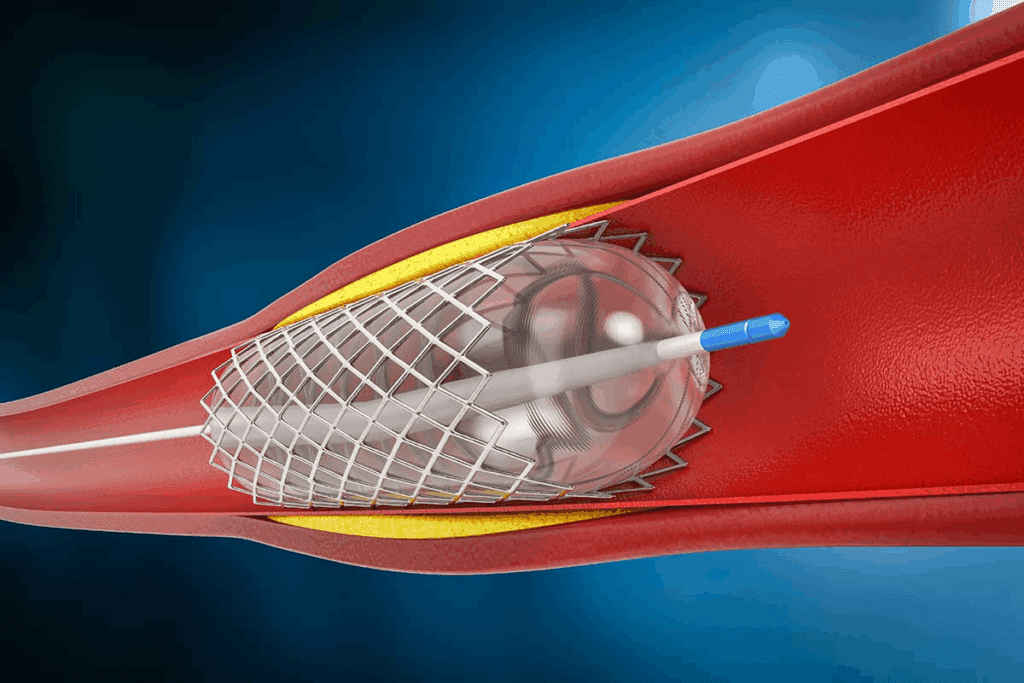

RFA uses radio waves to heat up and stop nerves. This method blocks pain signals to the brain. A special needle delivers the energy to the nerves.

RFA targets and stops pain nerves. A doctor uses X-rays to guide a needle to the nerves. Then, radio waves heat up the nerve, stopping it from sending pain signals.

“Burning nerves” in back pain relief is a precise medical technique called radiofrequency ablation (RFA). It uses radiofrequency energy through a needle to heat and disrupt pain-signaling nerves. This gives relief to those with chronic back pain.

The Mechanism of Nerve Disruption

Radiofrequency ablation heats nerves with radiofrequency waves. This heat stops the nerves from sending pain signals to the brain. This leads to less or no pain.

To start, a special needle electrode is placed near the nerve under imaging. The electrode sends out radiofrequency energy. This heats the tissue around the nerve, stopping it from working. This precision in targeting makes RFA different from other pain treatments.

Precision and Control in the RFA Procedure

RFA is precise because it targets specific nerves for pain. This is done with advanced imaging like fluoroscopy or ultrasound. This precision helps avoid harming other tissues.